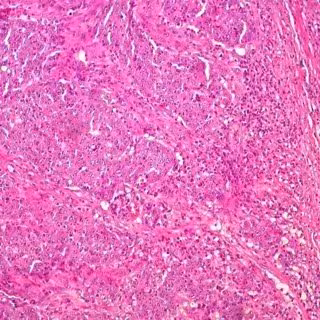

Científicos han identificado una combinación de bacterias que parece aumentar el riesgo de cáncer de colon. A través de una serie de experimentos en ratones, consiguieron identificar formas en que las dos especies de bacterias promueven la inflamación y descomponen la capa de moco del colon.

La investigadora Christine M. Dejea, del Instituto Bloomberg-Kimmel de Inmunoterapia del Cáncer de la Facultad de Medicina de la Universidad Johns Hopkins, en Baltimore, Maryland, Estados Unidos, y sus colegas comenzaron analizando muestras de tejido de pacientes con una afección genética asociada con un mayor riesgo de desarrollar pólipos precancerosos en el colon, llamada poliposis adenomatosa familiar (FAP, por sus siglas en inglés).

A diferencia de las muestras de pacientes con pólipos esporádicos, las muestras de FAP contenían parches de bacterias en las que 'Escherichia Coli' y 'Bacteroides fragilis' (ETBF) eran particularmente frecuentes, un resultado confirmado a través de un mayor conjunto de datos de muestras de pacientes con FAP.

Curiosamente, 'E. coli' y 'ETBF' expresan genes asociados con un mayor daño del ADN y tumorigénesis, respectivamente. Cuando los científicos implantaron estas bacterias de pacientes con FAP en ratones, descubrieron que los roedores con una sola especie desarrollaron pocos tumores, mientras que los animales que fueron colonizados con ambas especies bacterianas fueron sustancialmente más propensos al cáncer invasivo y la muerte.

A través de una serie de experimentos, Dejea y sus colegas encontraron que ETBF altera el microambiente del intestino al reducir el moco e inducir una respuesta inflamatoria, lo que ayuda a 'E. coli' a colonizar el intestino también. Con base en estos resultados, los autores sugieren que la eliminación de estas bacterias del revestimiento mucoso de los pacientes con FAP temprano en la vida puede ser beneficioso.